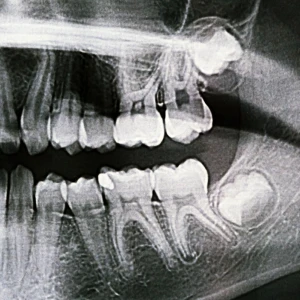

Wisdom teeth in San Francisco X-ray showing impacted upper and lower wisdom teeth

A frequent issue linked to wisdom teeth is impaction. An impacted wisdom tooth occurs when the tooth cannot fully break through the gum line due to obstruction from bone or nearby teeth. Impacted teeth may remain completely hidden beneath the gums or partially emerge, often causing swelling, jaw stiffness, and discomfort.

Impacted wisdom teeth can also place pressure on surrounding teeth. Over time, this pressure may affect alignment and lead to crowding, especially in patients who previously underwent orthodontic treatment.